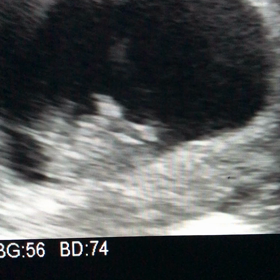

• D41  排卵から19日目  ※胎嚢確認の画像

D41 排卵から19日目 ※胎嚢確認